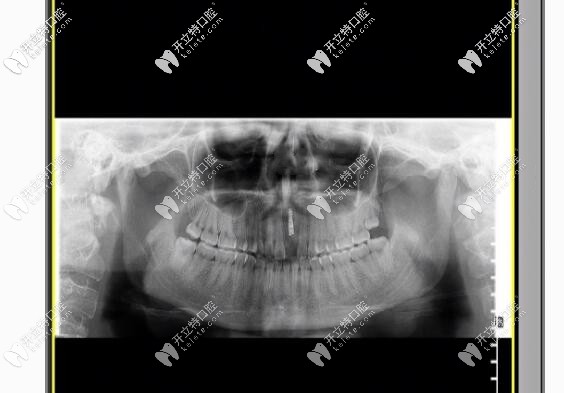

拍片圖示